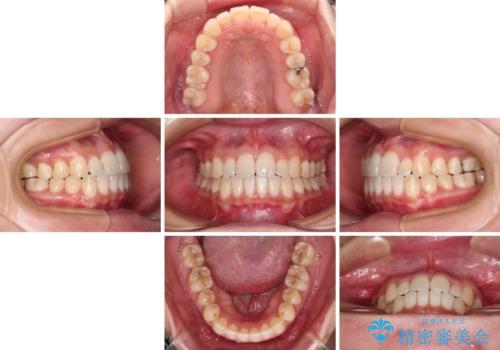

すきっ歯とオープンバイトをインビザラインで改善

- インビザライン

- 1年2ヶ月

- 前歯の上下スペースと前歯の隙間を気にして来院された患者様です。

インビザラインにより上下の前歯の隙間を閉じていくこととしました。

上下の隙間に舌が入り込むことが、すきっ歯やオープンバイトの原因であったため、舌の筋肉のトレーニングも並行して行い、後戻りの抑制を図りました。